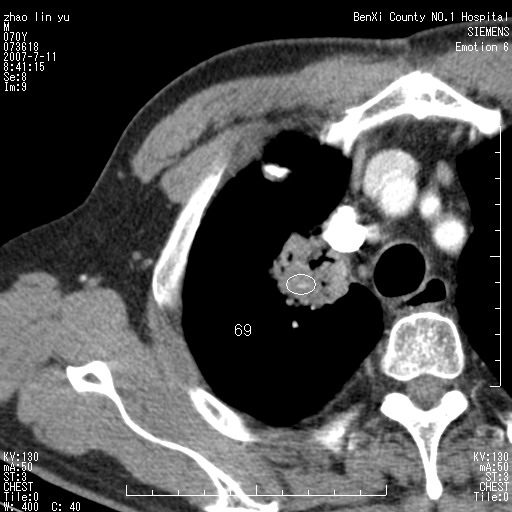

以下是引用王靖旗在2007-7-10 17:12:00的发言:[br] 男、70、咳嗽两个月,半年前换瓣手术,胸片未见异常,于昨天行x片发现右肺上野大片影,行ct扫描,这里是减薄图像,余肺正常。明天晚上会有增强扫描片,到时我会上传。[br][br] 冠状位请大家细看,应该是有意义的,[br][br] 请大家先看平扫发表意见。[br][br]

以下是引用zhangzhongshou在2007-7-10 21:43:00的发言:[br]右肺上叶周围型肺癌,以孤立型细支气管肺泡癌可能性大。